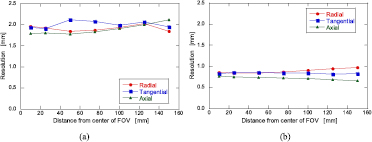

The spatial resolution was assessed according to NEMA NU 4-2008 for small animal PET. A 0.25 mm diameter 22Na point source (MMS09-022: EZIP, USA) of approximately 0.4 MBq was placed at distances of 10, 25, 50, 75, 100, 125, and 150 mm from the center of the transaxial FOV with both horizontal and vertical lines, where three axial positions with the center, 1/4, and 3/8 of the axial FOV from the center of the FOV were measured. The measurement time for each position was 5 min, and more than 5 M counts were obtained. The image reconstruction was performed both in 2D FBP and LM-DRAMA in the HR-mode. The voxel sizes were 0.3 × 0.3 × 0.3 mm3 in both 2D FBP and LM-DRAMA in the HR-mode, respectively. In LM-DRAMA, the iteration number was four, and an image-based point-spread function (PSF) (Reader et al 2002) of 1.8 mm in all directions was used. To obtain FWHM values, profiles of point source images were interpolated and analyzed according to NEMA NU 4-2008.

Figure 6(a) shows the spatial resolutions reconstructed with 2D FBP at the axial center position. The resolutions ranged from 1.8 mm to 2.1 mm in the whole FOV. These observations indicated uniform resolutions in the whole FOV of 330 mm by adopting four-layer DOI detectors. Figure 6(b) shows the spatial resolution reconstructed with the LM-DRAMA in the HR-mode in the axial center position. The resolutions of the whole transaxial FOV for the HR-mode were uniformly around 0.9 mm. The axial resolutions in the whole FOV were also uniform, and were slightly better than the transaxial resolutions. The results for 1/4 and 3/8 of the axial FOV from the center of the FOV were not different for that in the axial center.

Figure 6. Reconstructed spatial resolution as a function of the distance from the center of the FOV for (a) 2D FBP and (b) LM-DRAMA in the high-resolution (HR)-mode.